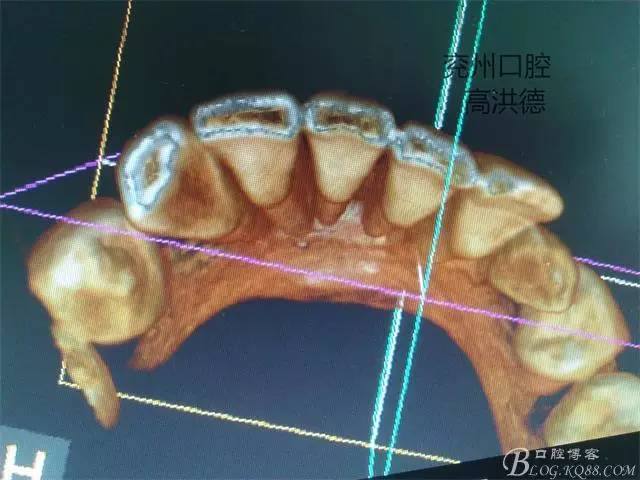

三維成像

冠狀位,舌側觀